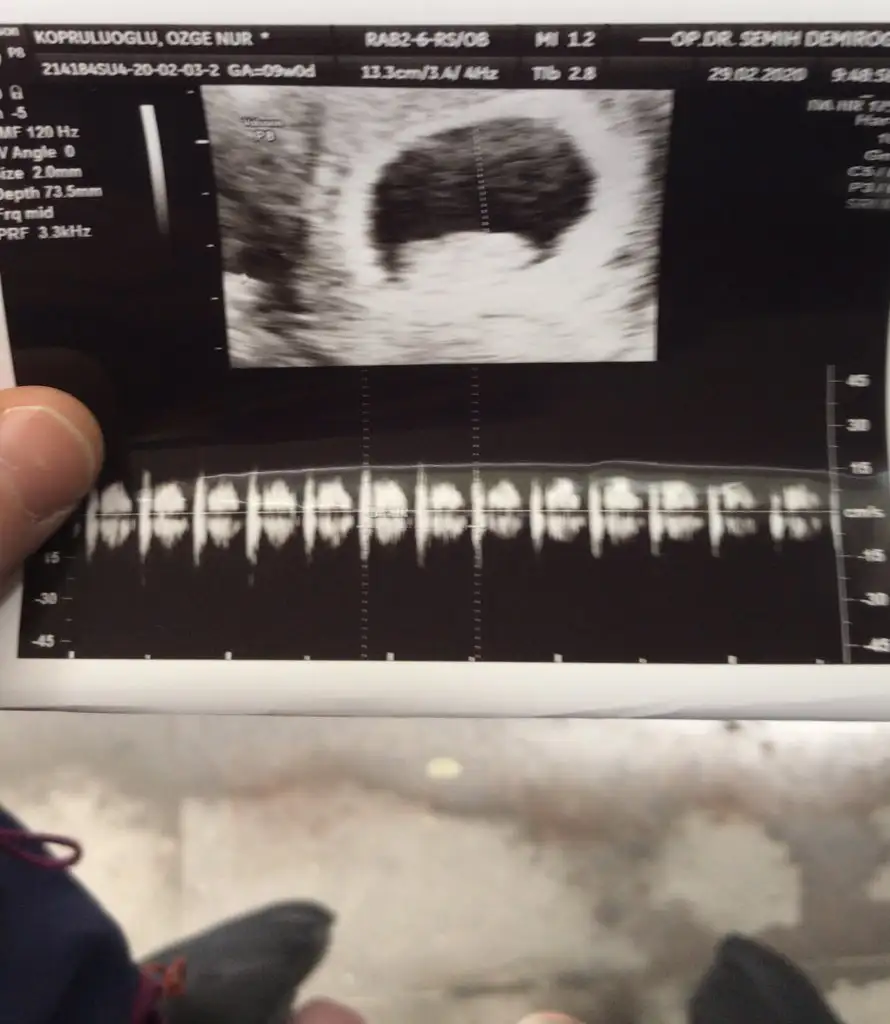

Maşallah canımHanımlar merhaba :) bende dün bebeğimi gördüm hepinize nasip olsun inşallah :)

Hadi bakalım güzel haberlerini bekliyoruz yaramaz minigininBen iyiyim Allaha sukur agrilarim kesildi ama ayaga kalkinca belime vuruyor hafif hafif. Persembe gunu devlet hastanesine gidicem ama yarin ozeldeki doktorumu bi ziyaret edicem cunku devlette ultrason goruntusunde gorulen kalp atisinin sesinin duyulmamasi tedirgin etti beni.

Gümbür gümbür duyacaksın inşallahMerhaba kızlar

Önümüzdeki hafta hepimiz güzel haberlerle doldururuz burayı inşallah. Benim yarın sabah kalp sesini dinlemek için randevum var ama kalp sesinin yanında kanama alanı azalmıştır inşallah diyorum